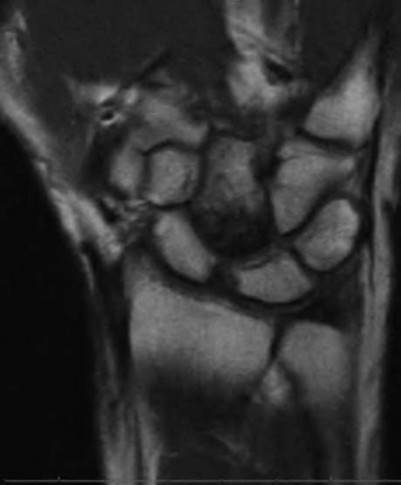

A 20-year-old park ranger trips and falls onto his right wrist with the wrist in extension and pronation. The local urgent care orders both radiographs and a CT, which you review and determine to be normal. The patient complains of ulnar-sided wrist pain. On exam, his tenderness is localized to the fovea. Ulnar deviation also causes him pain. There is no snapping sensation with wrist supination, flexion, and ulnar deviation. He otherwise has 5/5 strength to his first dorsal interosseous muscle with 4mm static two-point discrimination on the ulnar side of the 4th digit. Which of the following injuries is most likely responsible for his symptoms and exam?